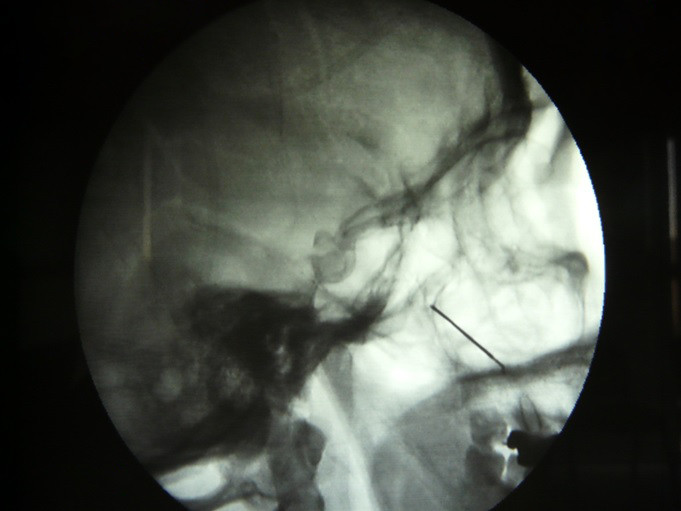

Fig.4. Adecuada colocación de la aguja en su trayecto infra cigomático y penetración en la fosa Ptrigopalatina

Fig.5. En esta proyección lateral se observa la aguja posicionada en la fosa ptrigopalatina como referencia guía y la Crio sonda colocada en la cavidad para realizar la crio lisis.